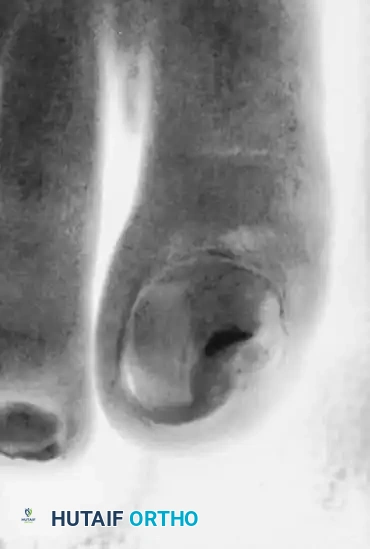

Fig. 84-24A: Onychomycosis and Onychogryposis. Severe "Ram’s horn" nails in a 90-year-old man, demonstrating the extreme hypertrophy that threatens the underlying soft tissue envelope.

Dystrophic and deformed nails, particularly in elderly and diabetic populations, represent a significant clinical challenge. These conditions can be difficult to manage at best and catastrophic at worst, especially when associated with an insensitive, neuropathic foot. Onychogryposis, commonly referred to as a "ram’s horn nail," is characterized by asymmetrical hypertrophy of the nail plate, leading to a thick, curved, and opaque deformity.

In diabetic patients with peripheral neuropathy, the hypertrophic nail acts as a rigid lever arm. Normal shoe wear applies pressure to the dorsal aspect of the dystrophic nail, which is transmitted directly to the underlying nail bed. In an insensitive foot, this repetitive microtrauma rapidly progresses to pressure necrosis, subungual ulceration, and contiguous osteomyelitis of the distal phalanx.